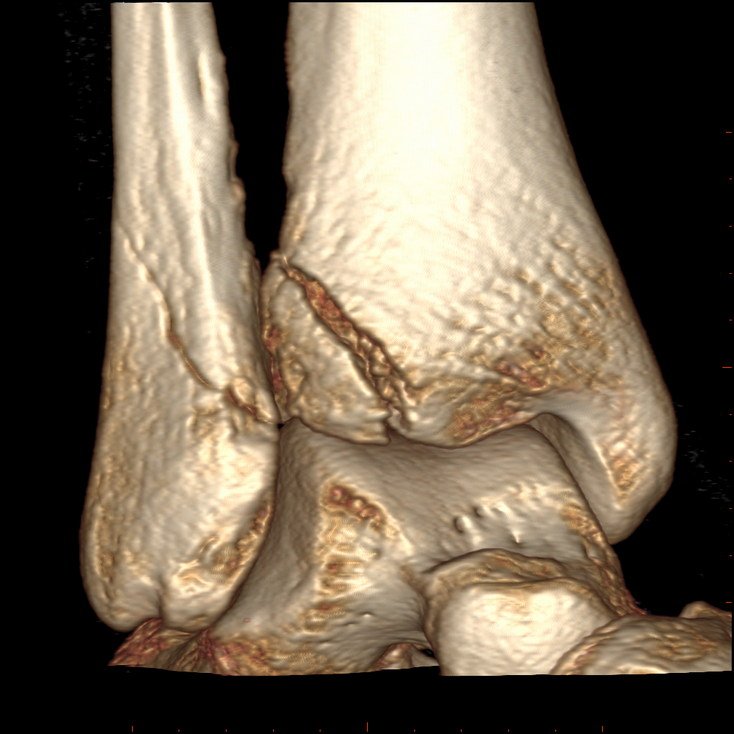

3D CT Ankle Fracture